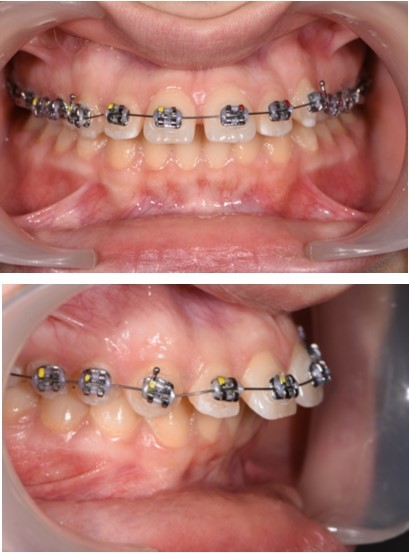

Figure 4.Treatment start - Orthodontic appliance on the upper arch, Roth 022" prescription.

Treatment started with orthodontic appliances on the upper arch, Roth 022" prescription. In order to achieve a better retraction of the upper teeth, first bicuspids were extracted. Retraction of the upper incisors with elastics chains placed from crimpable hooks to orthodontic implants.